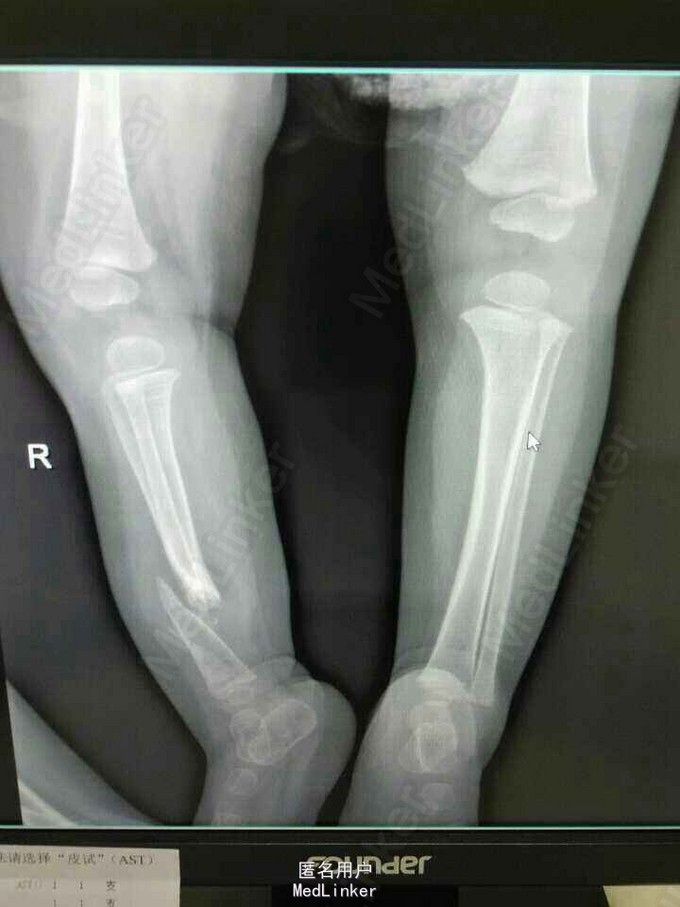

患女1岁8个月,患者母亲诉小孩出生时右小腿畸形,1岁时学走路跌倒后哭闹数天,小腿肿胀去医院检查示右胫腓骨折,稍做固定,1岁3个月时复查骨折未愈合,考虑先天性胫骨假关节,行手术治疗,现术后5个月复查未愈。目前小儿不能行走。

右下肢短缩约2cm,右小腿畸形,肌力检查不配合,

神经纤维瘤病,先天性胫骨假关节。该患者经过讨论及与家属多次沟通愈后情况,行病灶切除,取母体骨移植,AO锁定钢板内固定,暂时管型石膏外固定,并订制支具